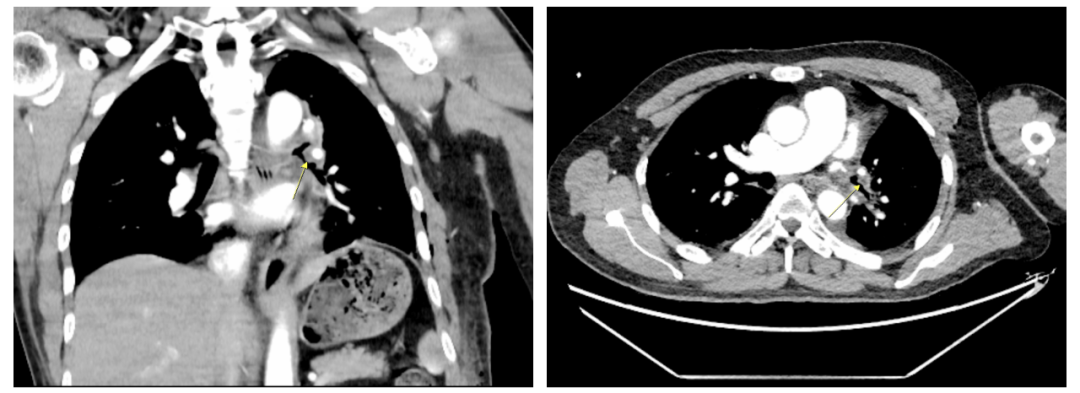

新辅助化疗前胸部CT检查

新辅助化疗后胸部CT检查